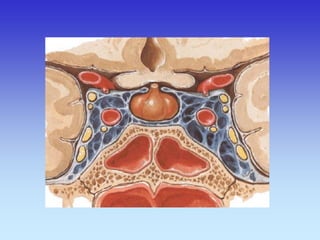

MOŽDANE OVOJNICE

CEREBRPOSPINALNI LIKVOR